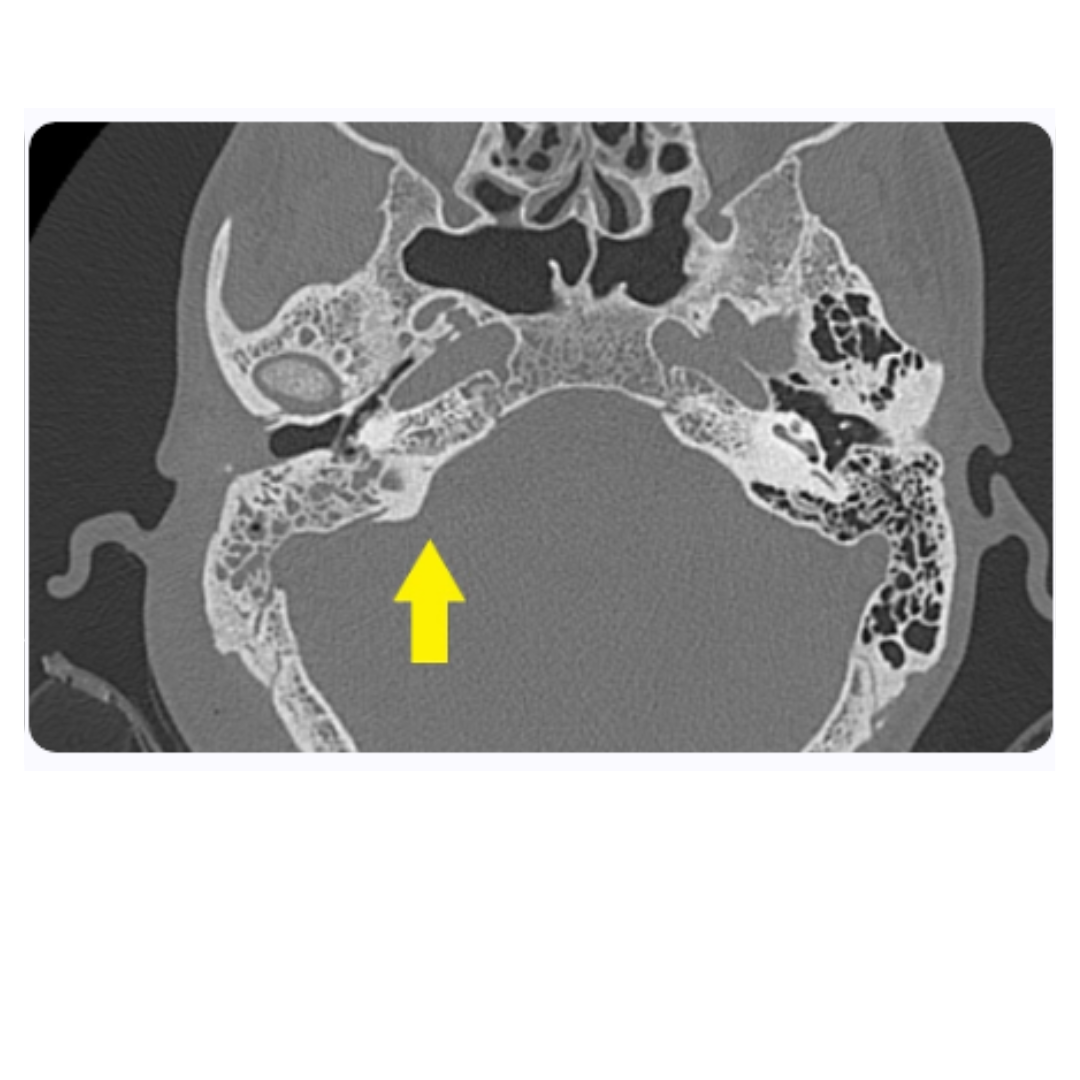

9. Estudios de imagen en el diagnóstico de la leucemia linfocítica aguda

Resonancia magnética cerebral

Tomografía computarizada de tórax

La tomografía computarizada (TC) de tórax permite la evaluación de complicaciones pulmonares en pacientes con LLA. Especificidades como infiltrados pulmonares o la presencia de masas mediastínicas pueden ser indicativos de enfermedad agresiva o complicaciones infecciosas. Por lo tanto, la TC es un componente indispensable del arsenal diagnóstico, proporcionando información valiosa para el manejo integral del paciente.